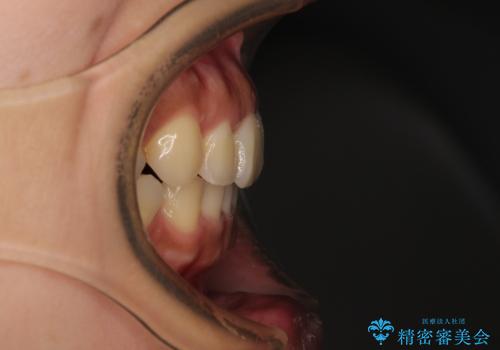

【モニター】歯列が狭くデコボコが気になる 急速拡大装置を用いたインビザライン矯正

- 奥歯の咬み合わせと治療を放置したまま奥歯を気にして来院された患者様です。

上顎骨の幅が下顎骨よりも小さいので、拡大装置により骨幅を広げて上下関係を改善し、その後インビザラインにて歯並びを整えることとしました。

土台のまま放置されていた歯は土台の状態で咬み合っていましたが、急速拡大を行った際に咬み合わせが著しく挙上されたため、その際に土台を大きくすることで咬み合う歯との距離を確保しました。